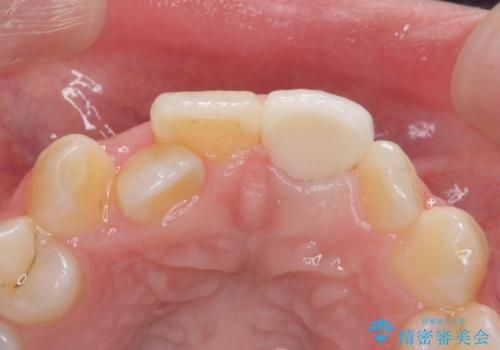

前歯の見た目が気になる。

- 前歯の見た目が気になるとの事で来院。

根の治療のやりかえは希望されなかったので土台だけやりかえを行い、ジルコニアクラウンで治療を行いました。

- ジルコニアクラウンスタンダード・仮歯・ファイバーコア 18.7万円費用は治療当時の料金となります

綺麗な被せ物が入り大変満足して頂けました。